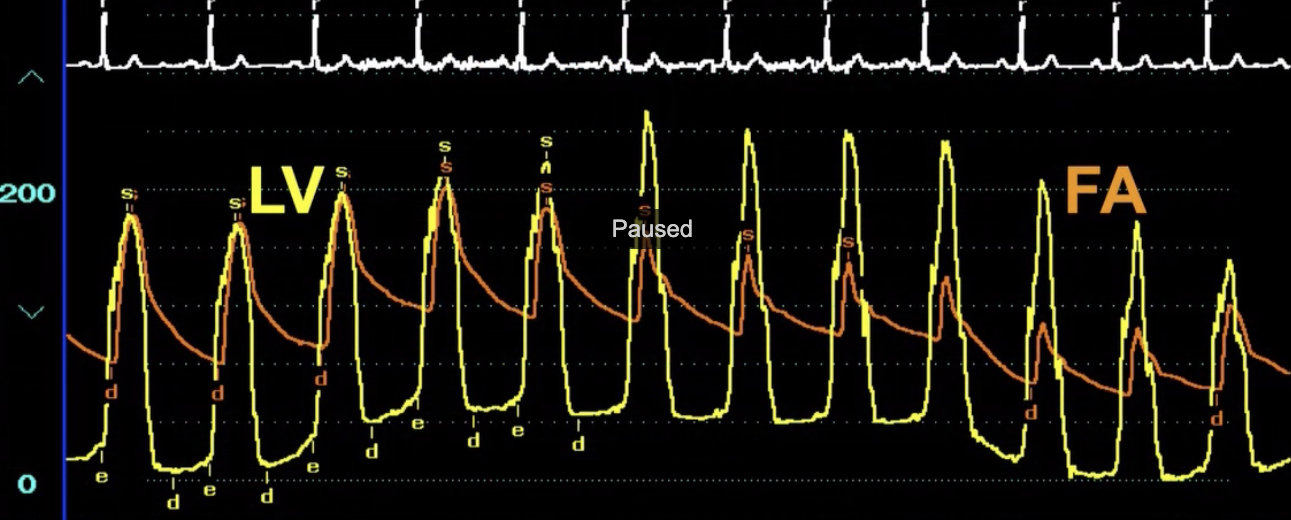

Describe the findings

AS